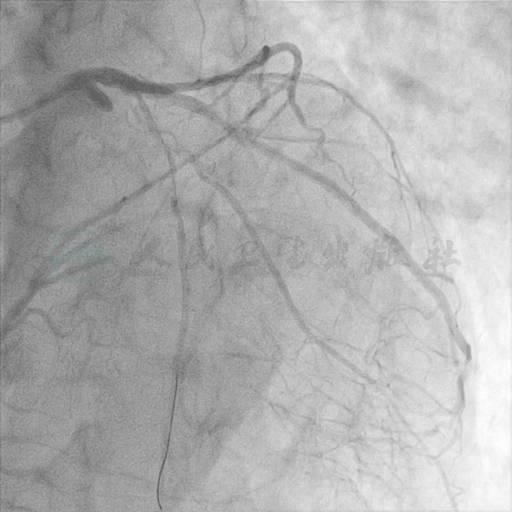

冠状动脉造影结果

选用右侧桡动脉径路,6F血管鞘,TIGER造影导管。造影发现:冠脉分布呈右冠优势型,左主干近段局限偏心40%狭窄,LAD开口处100%闭塞,远端隐约可见来自RCA的侧支循环,LCX近段局限偏心狭窄约50%,OM1开口处局限偏心狭窄约70%,远段血流TIMI 3级;右冠近段90%狭窄,中段100%闭塞,远端可见来自LCX及中间支的侧支循环供应,有一较大侧支循环(CC 2级,Rentrop 3级),后分叉前以远显影(图1~图5)。

图1 左主干近段局限偏心40%狭窄

图2 LAD开口处100%闭塞,远端隐约可见来自RCA的侧支循环

图3 LCX近段局限偏心狭窄约50%,OM1开口处局限偏心狭窄约70%,远段血流TIMI 3级

图4 右冠近段90%狭窄,中段100%闭塞

图5 右冠远端可见来自LCX及中间支的侧支循环供应,有一较大侧支循环(CC 2级,Rentrop 3级),后分叉前以远显影